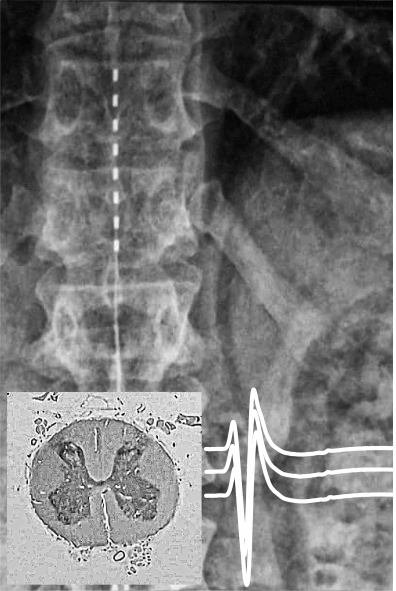

Our research focuses on deepening our current understanding of how movement is neurally controlled by the human spinal cord. At the basic science level, we are particularly interested in characterizing movement generators, known as locomotor circuits, in the human spinal cord - neuronal networks that have so far only been clearly identified in animals.

- Characterization of locomotor circuits in the human spinal cord

- Establishment of a scientific framework of electrical spinal cord stimulation

- Studies of the interaction between electrical neuromodulation and spinal cord circuits

- Pioneers in the development of transcutaneous spinal cord stimulation

- Pioneers in studies of epidural spinal cord stimulation in individuals with spinal cord injury

- Minassian K, Hofstoetter US, Dzeladini F, Guertin PA, Ijspeert A., 2017. The Human Central Pattern Generator for Locomotion: Does It Exist and Contribute to Walking? Neuroscientist, 23(6):649-663.

- Danner S, Hofstoetter U, Freundl B, Binder H, Mayr W, Rattay F, Minassian K, 2015. Human spinal locomotor control is based on flexibly organized burst generators. Brain, 138(Pt 3):577-88.